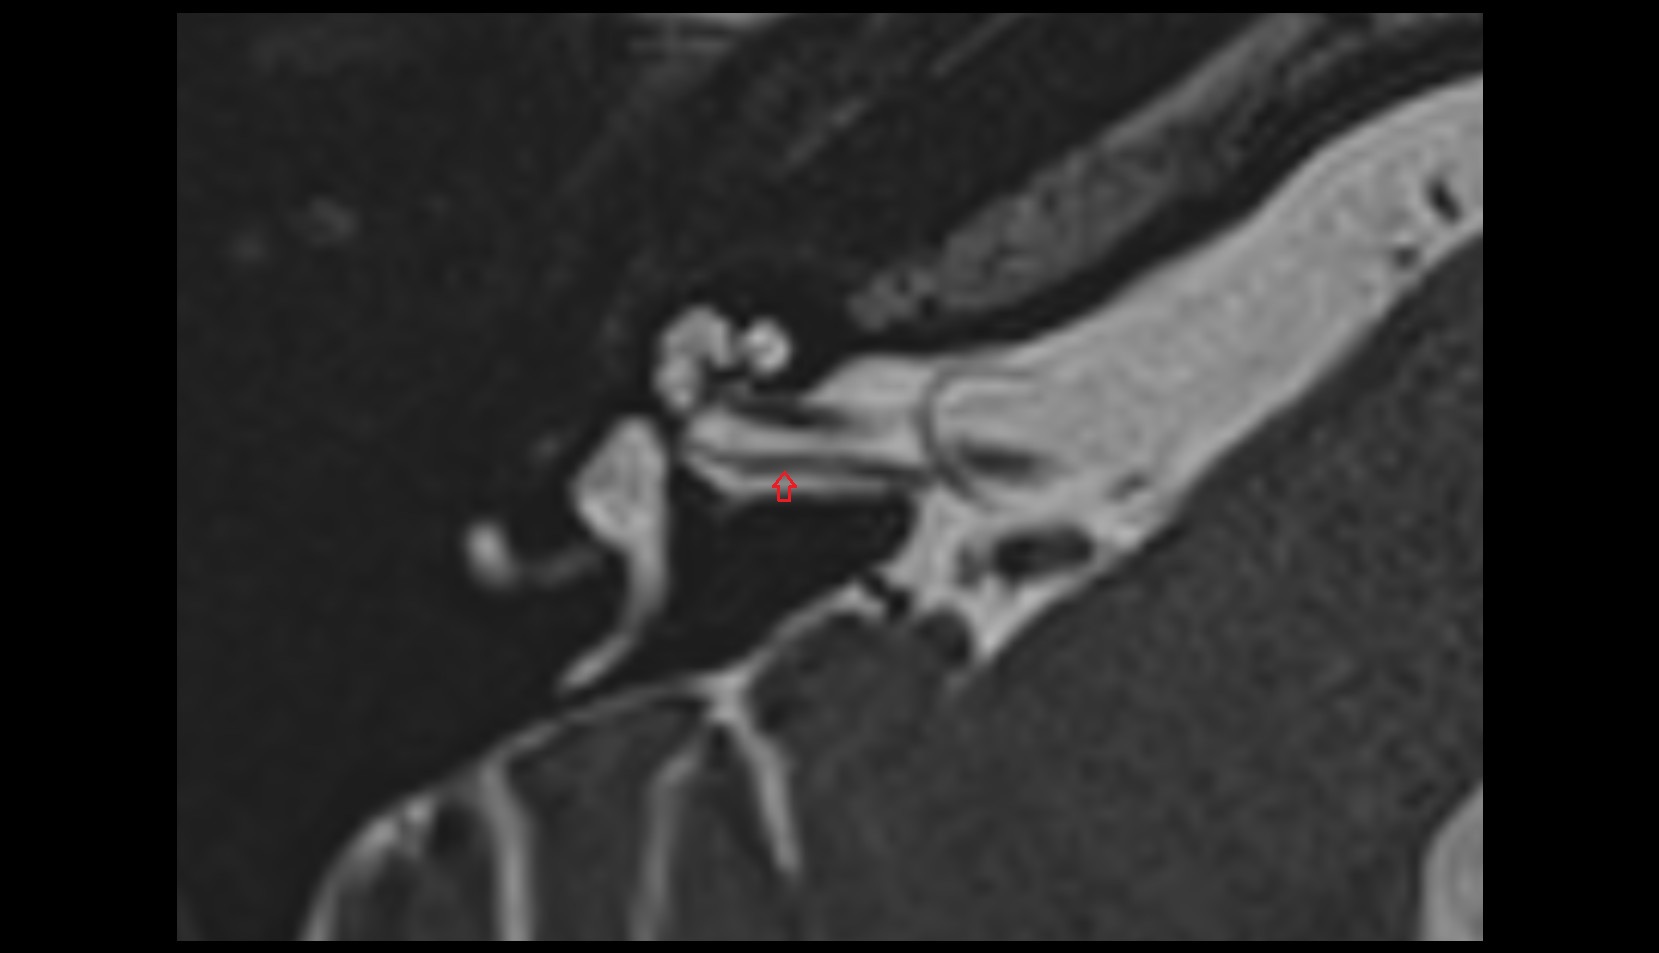

- Temporomandibular joint

- Articular disc of temporomandibular joint

- Articular eminence

- Mandibular condyle

- Mandibular fossa

- Superior head of lateral pterygoid muscle

- Inferior head of lateral pterygoid muscle